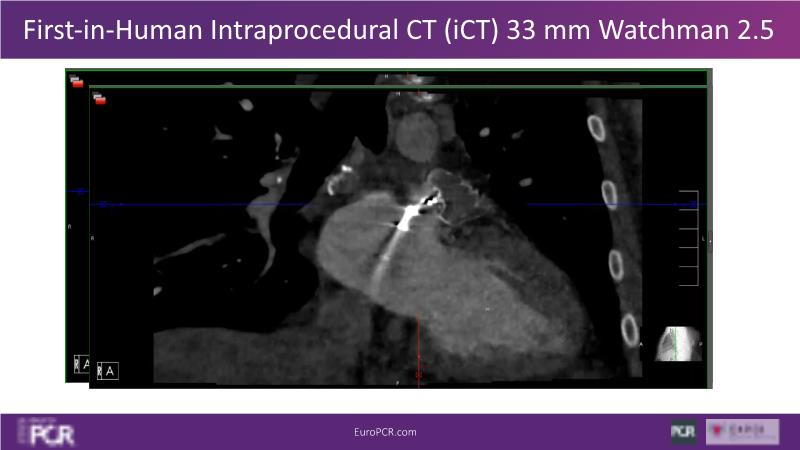

Explore this session to discover the latest innovations in interventional cardiology images, including the benefits of artificial intelligence and angio-CT in PCI/SHD procedures. Learn about Alphenix Evolve and the initial experiences with AI imaging in daily cathlab practice, alongside intraprocedural angio-CT guided LAAO, and engage in discussions on meaningful tools that can transform patient care.